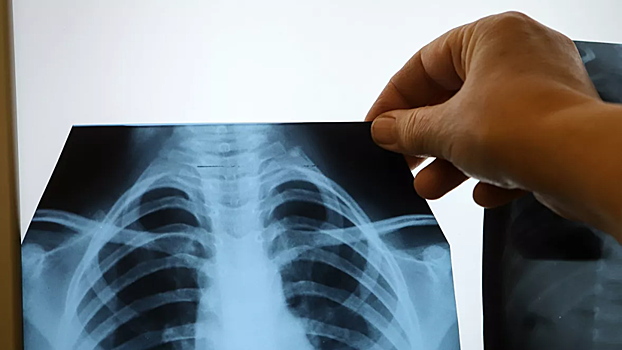

Эксперт прокомментировал сообщения о лечении COVID-19 с помощью рентгеновского излучения

Аллерголог-онкоиммунолог Даниил Щепеляев прокомментировал сообщения американских учёных о том, что рентгеновское излучение в малых дозах может вылечить коронавирусную пневмонию. «Малые дозы рентгеновских лучей могут помочь против коронавирусной пневмонии, но это всё равно, что лечить головную боль ударом кувалды по затылку. Вы её вылечите, только с какими последствиями», — заявил он в беседе с Nation News. Как пояснил эксперт, это просто усугубит ситуацию. По его словам, вирусный пневмонит и так очень часто переходит в фиброз, а лучевая терапия «переключит» воспаление в усиление фиброзных процессов. Ранее врач-онколог Андрей Пылев в беседе с НСН прокомментировал заявление Роспотребнадзора о том, что увеличение числа компьютерных томографий приводит к дополнительному облучению населения и может потенциально вызывать радиационно-индуцированные заболевания.